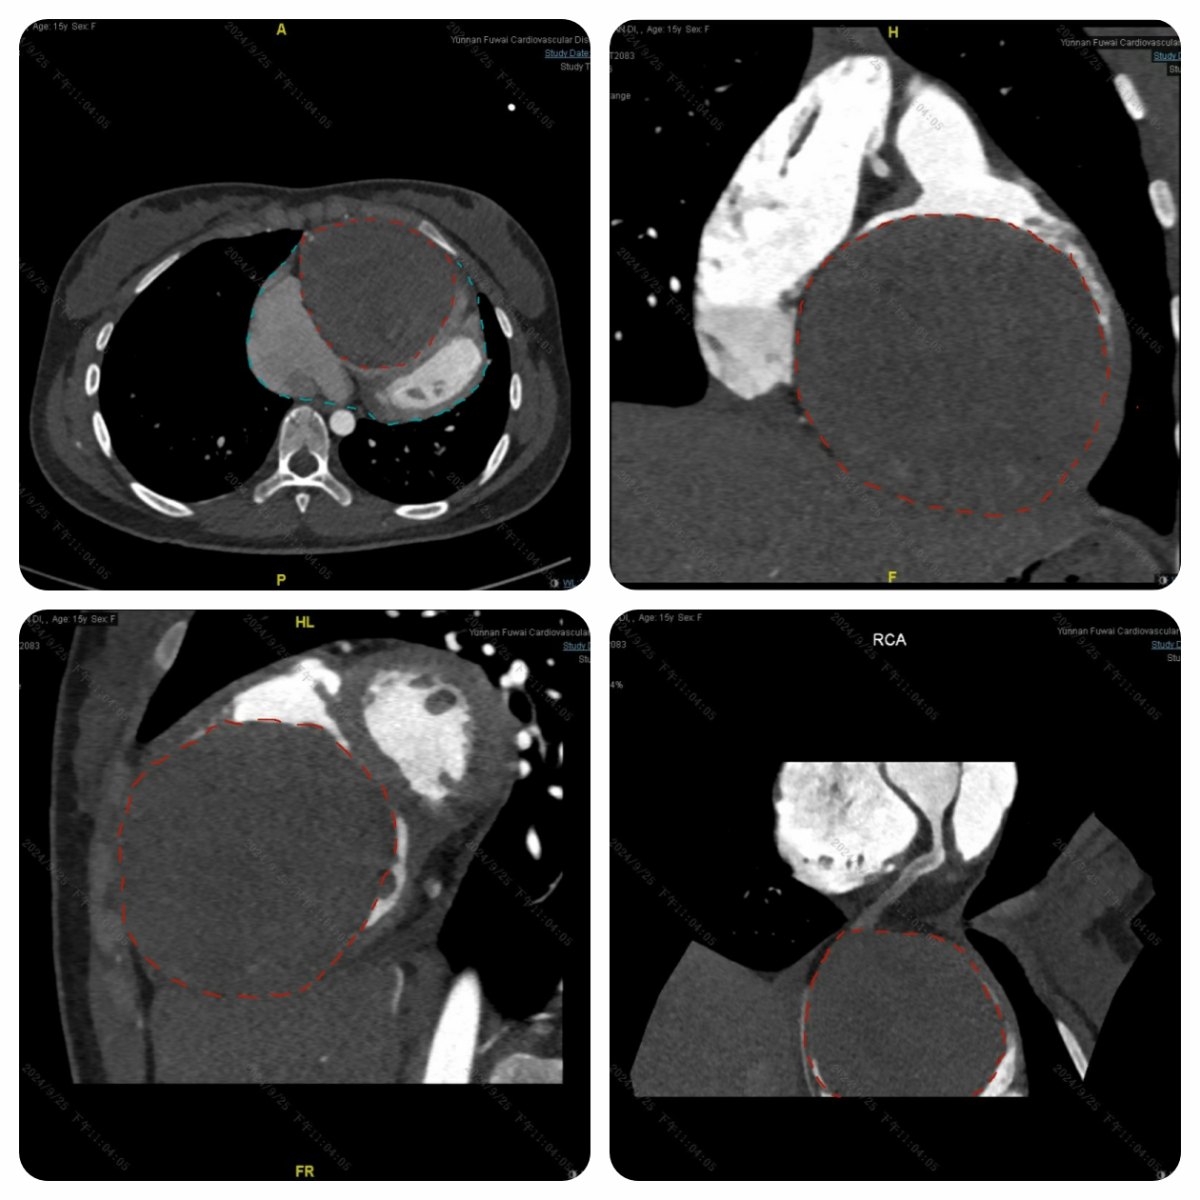

15 岁,本应是充满活力、肆意奔跑在青春赛道上的年纪,小迪(化名)却被胸口的憋闷与疲乏无情笼罩。两年间,这种不适如影随形,且愈发严重。在老家医院初步判断为心脏病后,心急如焚的家人带着小迪辗转来到云南省阜外心血管病医院(以下简称:云南省阜外医院)经过一系列全面的心脏检查,一个惊人的发现让所有人都捏了一把汗 —— 小迪的心脏上竟长出了一个犹如 “大炸弹” 般的东西。

随着心脏超声、心脏 CT、心脏核磁以及冠状动脉造影检查结果的陆续出炉,答案终于浮出水面:它源自小迪的右冠状动脉。

这颗 “炸弹” 就像一个贪婪的 “侵略者”,当发现它时,其直径已将近 10 公分,源源不断的血液从右冠状动脉涌入其中,持续压迫着心脏,小迪也因此愈发难受。冠状动脉上出现如此巨大的 “炸弹”,极为罕见。一旦这个 “炸弹” 哪天突然 “爆炸”,小迪年轻的生命将岌岌可危。